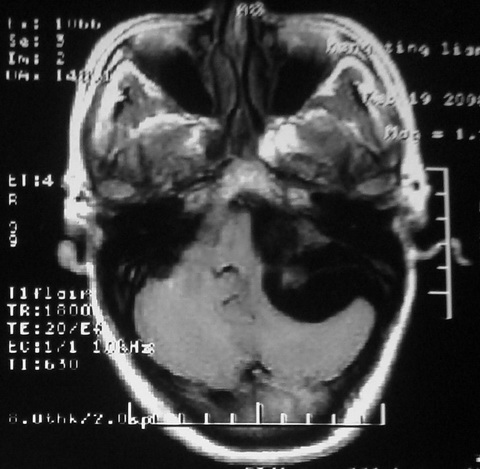

m,72,头疼,头晕两年,伴视力模糊三月,饮食呛咳两天。pe:颈部抵抗,左眼突出,左眼瞳孔约3mm,对光反射消失,双眼失明,伸舌困难,双肺呼吸音粗,心率110次/分,左上肢肌力i级,左下肢屈曲,肌张力高。现有08年2月19mri平扫及10年2月8日mri增强请会诊。ct病灶呈低密度伴散在点、片状等密度区,无明确钙化(无ct片资料可供上传)。[

脑外肿瘤,囊实性,环状不规则强化,内听道扩大,考虑神经源性肿瘤

左侧桥小脑区占位伴梗阻性脑积水----考虑 1神经鞘瘤 2室管膜瘤。

左侧桥小脑区神经鞘瘤伴梗阻性脑积水。

听神经瘤

左侧桥脑小脑角区肿瘤并脑积水,考虑听神经瘤,脑膜瘤?

考虑听神经瘤

左侧桥脑小脑角区肿瘤并脑积水,考虑听神经瘤,